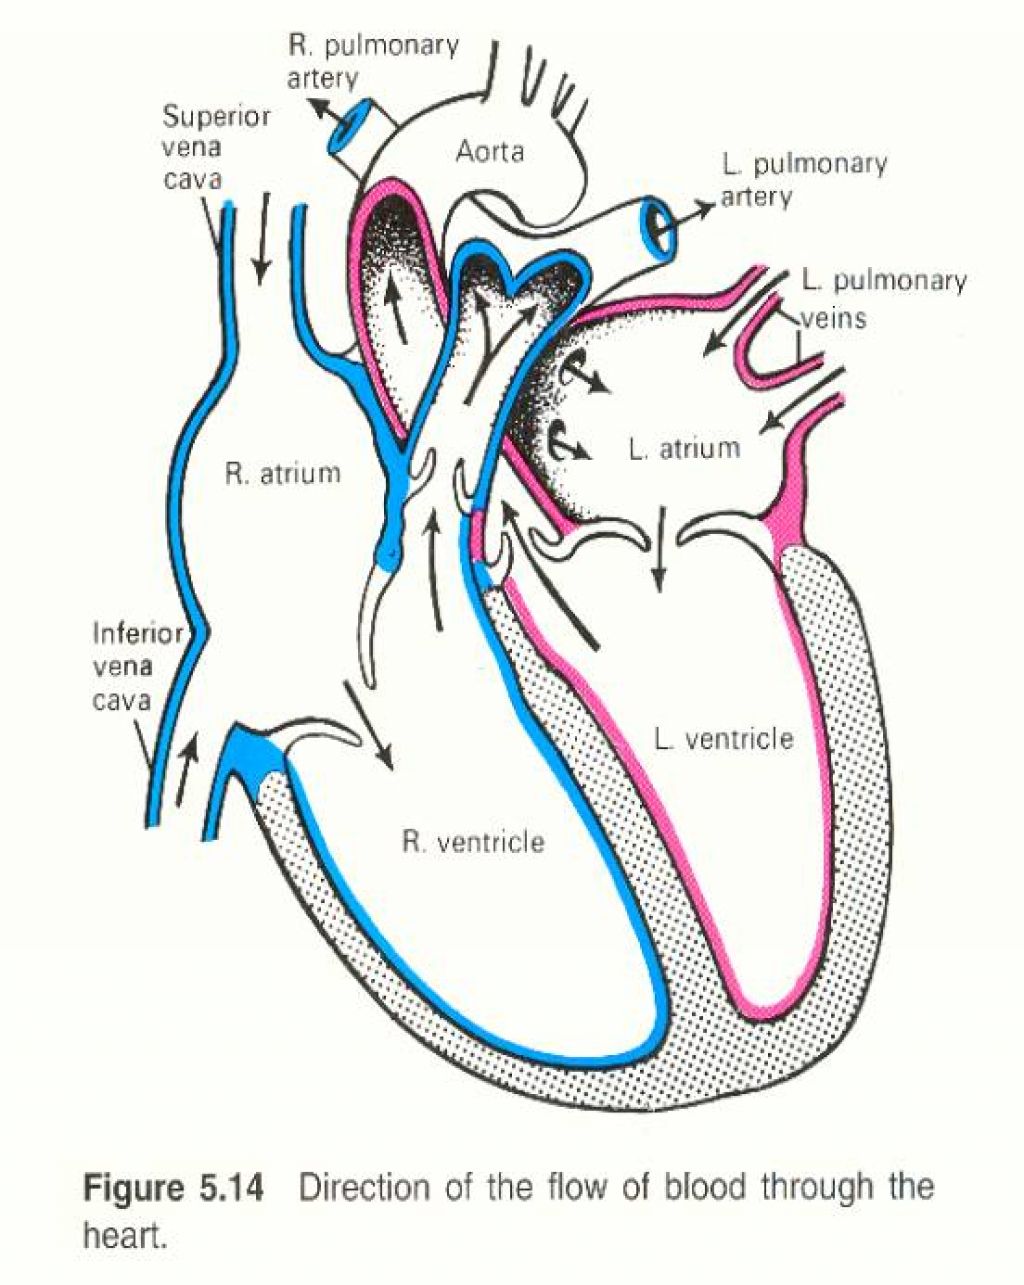

3d anatomy human heart  Show me a diagram of the human heart? Here are a bunch! - Interactive Biology, with Leslie Samuel

Sketch Human Heart Diagram Labeled - fallinlovewithyou-raura  Human Heart Anatomy 1 3D model | CGTrader

How the Human Heart Works | Safety and Health Solutions  3d human heart

Heart Diagram Human Heart Images Hd 3D - img-Badr  Real Human Heart Drawing at GetDrawings | Free download